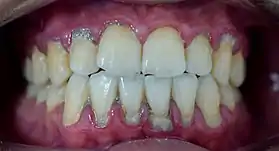

Calculus formation is associated with a number of clinical manifestations, including bad breath, receding gums and chronically inflamed gingiva. Brushing and flossing can remove plaque from which calculus forms; however, once formed, calculus is too hard (firmly attached) to be removed with a toothbrush. Calculus buildup can be removed with ultrasonic tools or dental hand instruments (such as a periodontal scaler).

Plaque accumulation causes the gingiva to become irritated and inflamed, and this is referred to as gingivitis. When the gingiva become so irritated that there is a loss of the connective tissue fibers that attach the gums to the teeth and bone that surrounds the tooth, this is known as periodontitis. Dental plaque is not the sole cause of periodontitis; however it is many times referred to as a primary aetiology. Plaque that remains in the oral cavity long enough will eventually calcify and become calculus.[15] Calculus is detrimental to gingival health because it serves as a trap for increased plaque formation and retention; thus, calculus, along with other factors that cause a localized build-up of plaque, is referred to as a secondary aetiology of periodontitis.